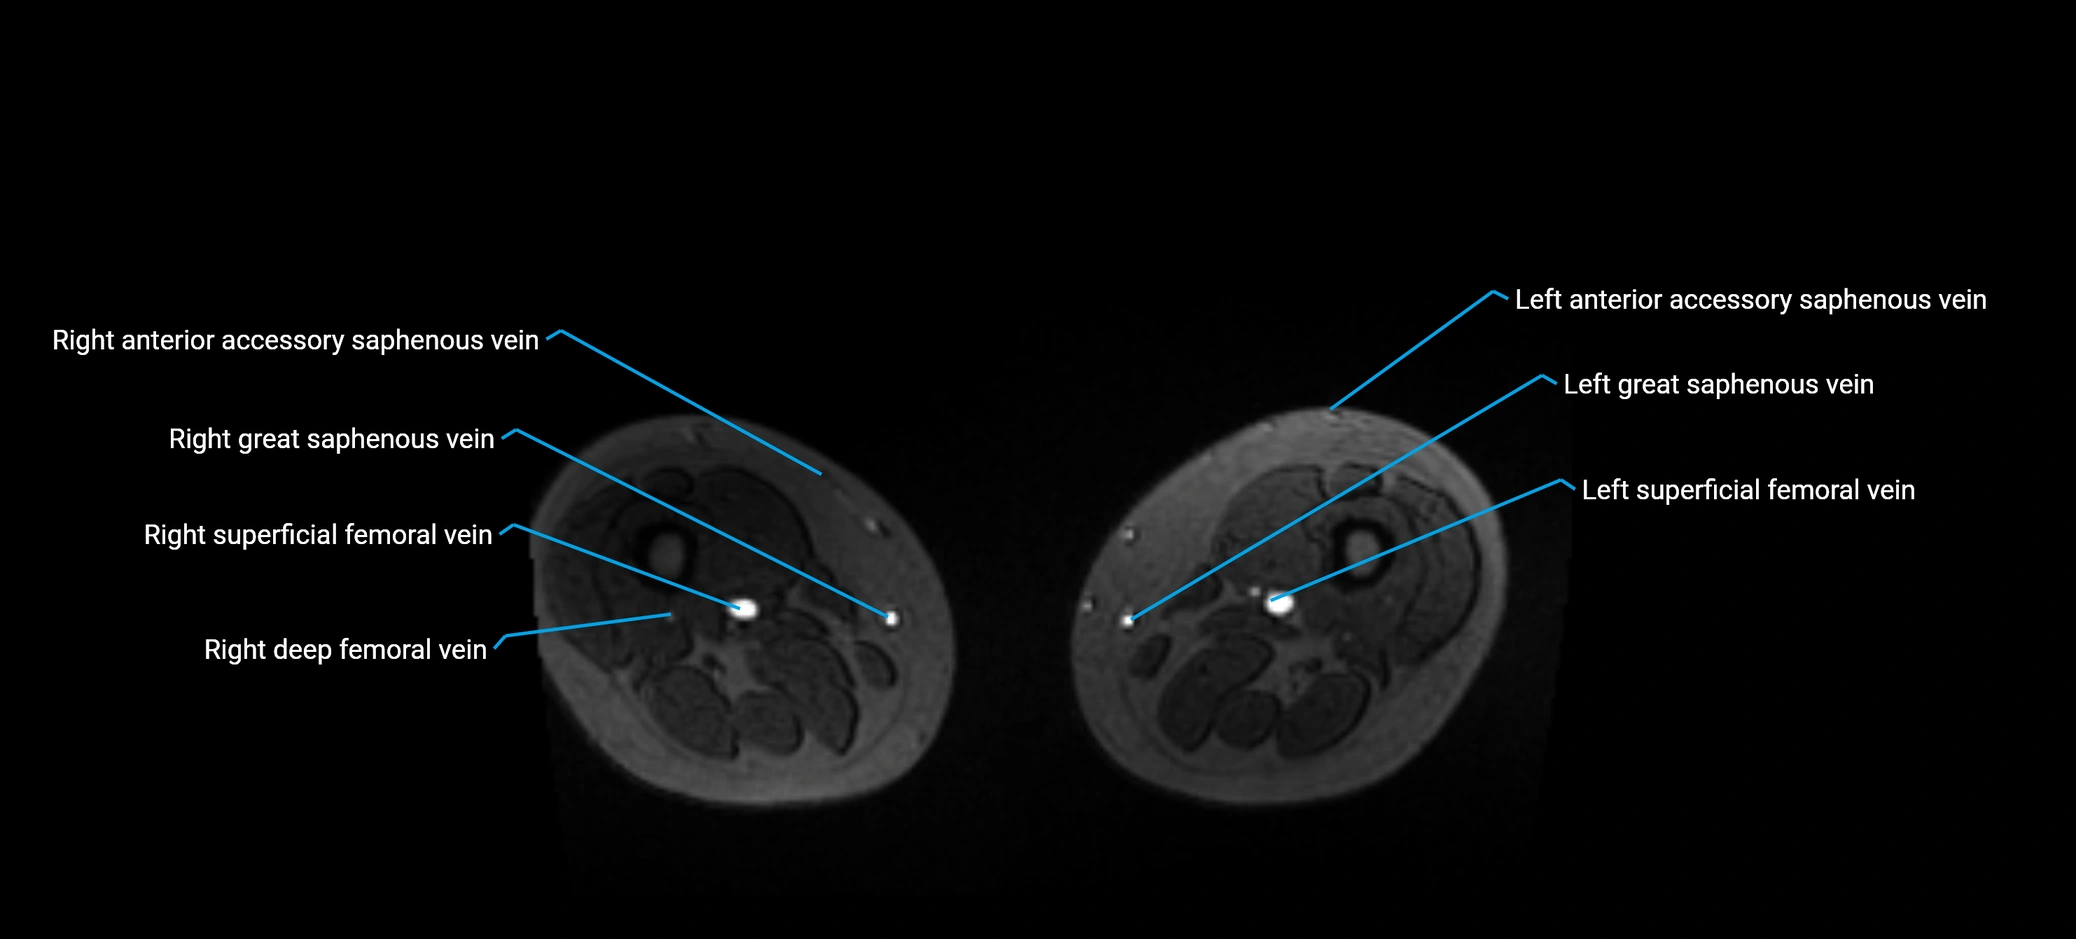

MRI image

image